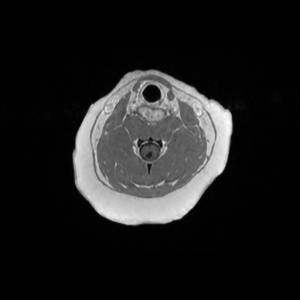

Main Gallery

Playing with a photo gallery function. It is possible to have multiple galleries, each within a namespace.